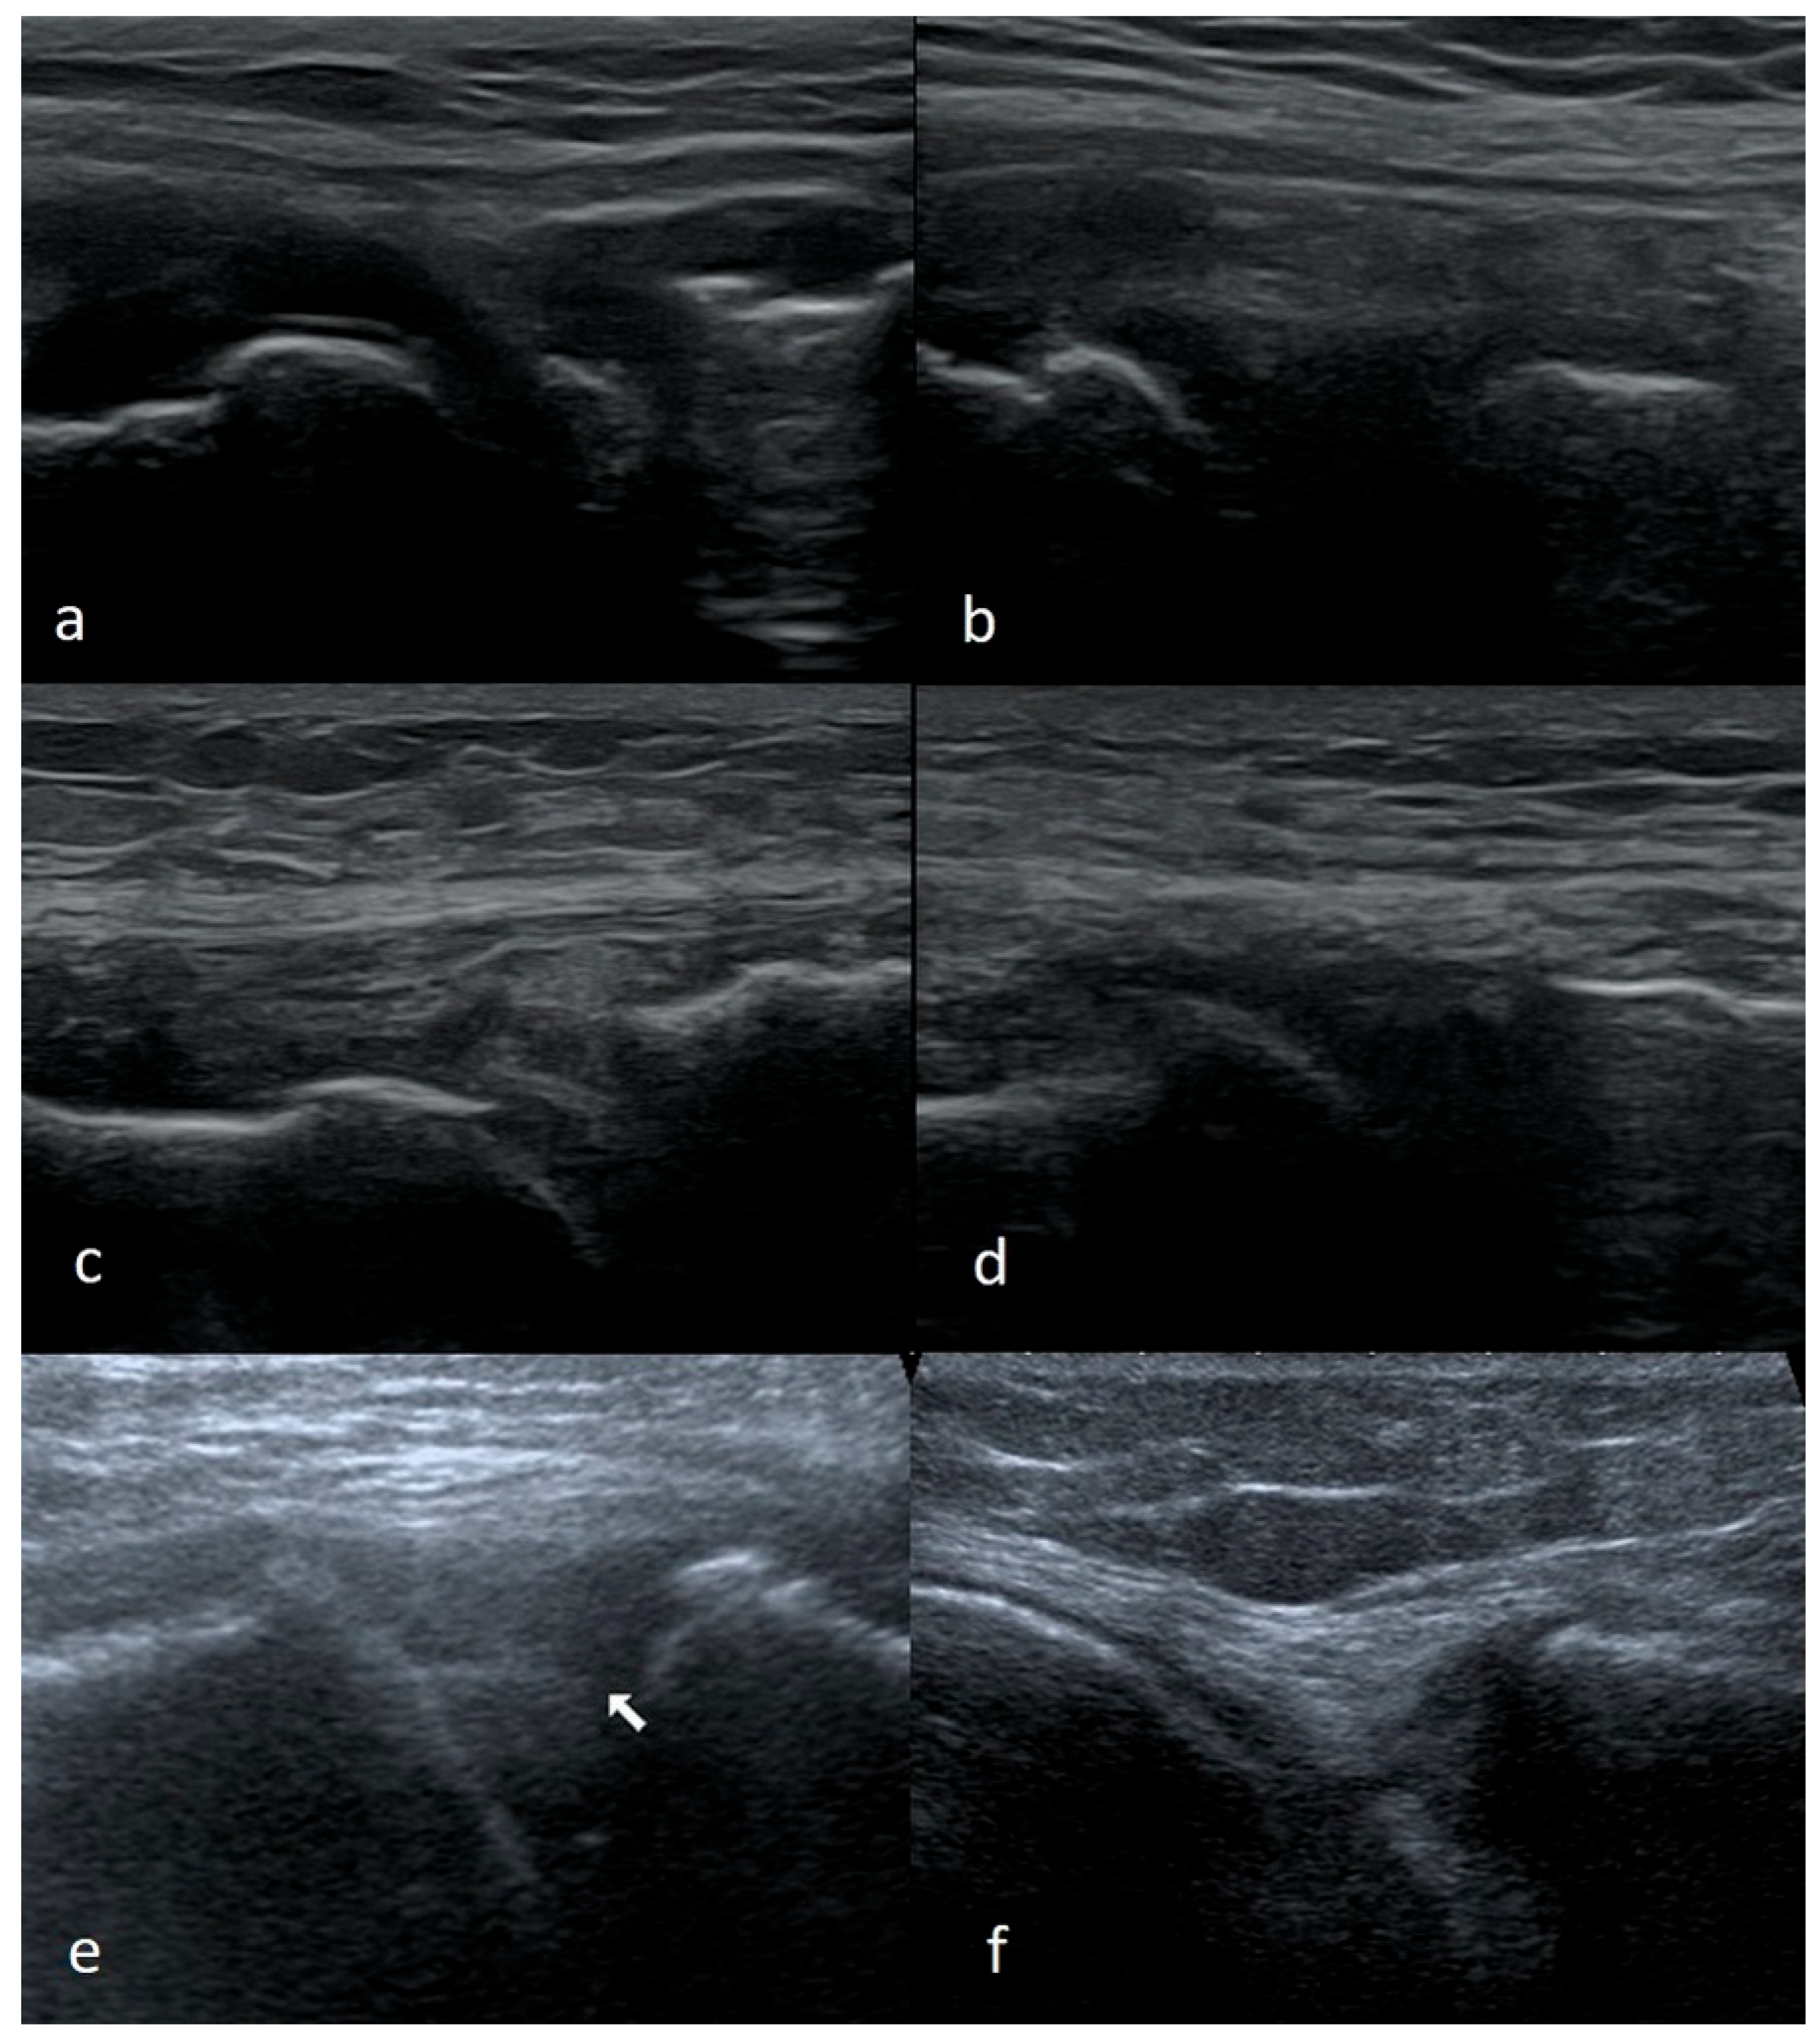

3.1.1. Meniscus Tears

3.1.2. Meniscus Cysts

3.1.3. Bucket-Handle Tears

3.1.4. Meniscal Flap Tears

3.1.5. Degenerative Changes of Menisci